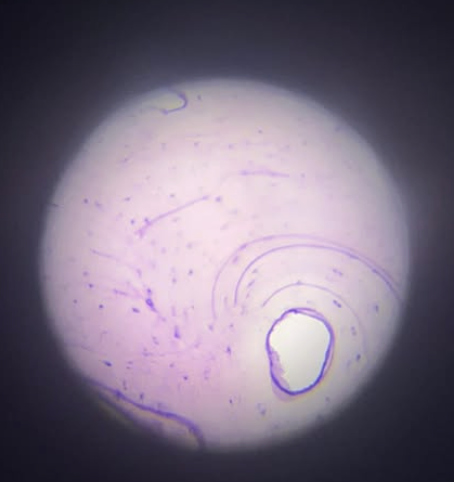

Cartilage

Cartilage Den

Oval

Cartillage cell shape?

Provides support, flexibility, shock absorption, and reduces friction at joints

Cartilage Function?

Chondrocytes

Cartilage Cell?